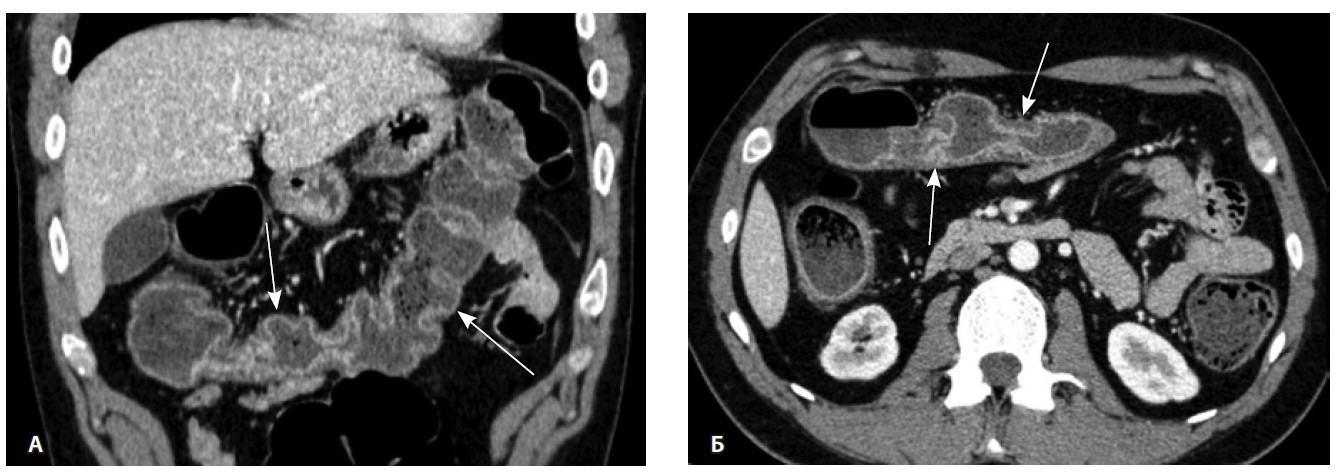

При мультиспиральной компьютерной томографии органов брюшной полости визуализировалась картина диффузного утолщения стенки толстой кишки с умеренным утолщением брыжейки и минимально выраженными явлениями лимфаденопатии в брыжейке (рис. 1).

Рис. 1. Мультиспиральная компьютерная томография органов брюшной полости с внутривенным введением контрастного вещества (йомепрол 350–100 мл), артериальная фаза: А – фронтальная проекция, Б – аксиальная проекция. Стрелками указано диффузное утолщение стенки толстой кишки и брыжейки